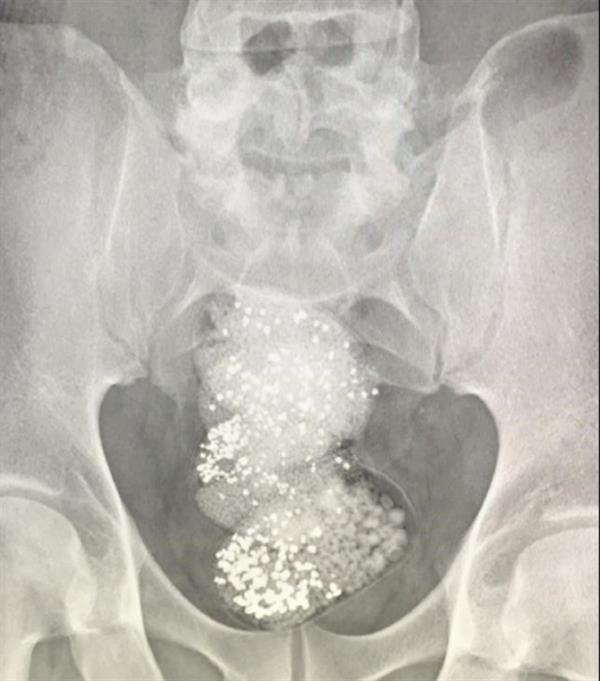

وتبيّن بعد عرض المسافر على جهاز كشف الأحشاء من قبل جمارك الشارقة قيامه بإخفاء 3 قطع بلاستيكية تحتوي على 297 غراماً من الألماس الخام تبلغ قيمتها نحو 90 ألف دولار.